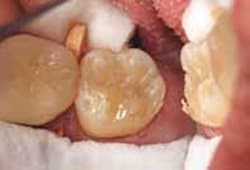

A 55-year-old female in good health with no pain or chief complaint presented to the office. After a thorough examination, it was determined that fractured amalgam restorations required replacement (Figure 5. Following the protocol previously described, the existing amalgams and caries were removed (Figure 6). The remainder of the procedure followed the clinical protocol described in Case Report 1, which included the placement of a matrix band to facilitate composite placement (Figure 7).

The bulk composite (Venus Bulk) was placed as the first bulk increment, staying below the enamel, and cured (Figure 8). The second and final increment was placed using a restorative composite (Venus Diamond), which was also cured (Figure 9) and appropriately finished (Figure 10.